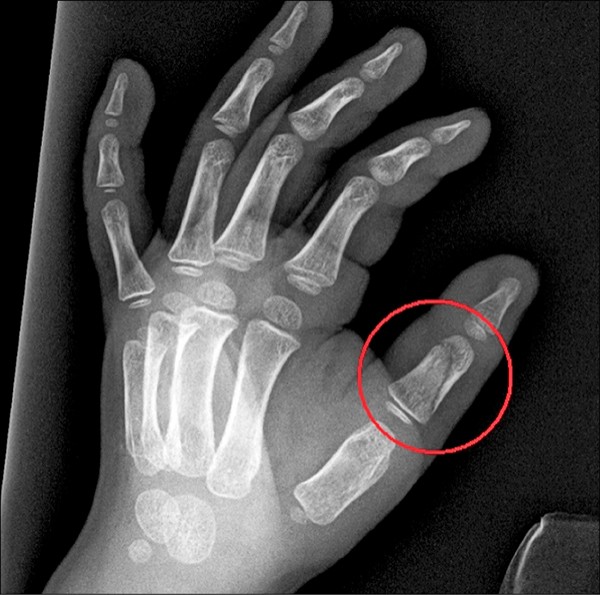

检方认定园长与老师3人对男童长期施虐,虐待手段曝光十分揪心,包括:四肢撑在椅子上变「桂河大桥」、喂吃发霉点心或坏掉食物、把男童的头压到水桶呛水、冬天冲冷水、用棍子打头与全身、处罚半蹲或交互蹲跳、捉脚绕圈抛飞害手指撞伤骨折、意指男童身上有病毒拒给水喝与如厕、命令孩子趴地上写字、逼洗厕所等十大酷刑,每一种都让妈妈好痛心。